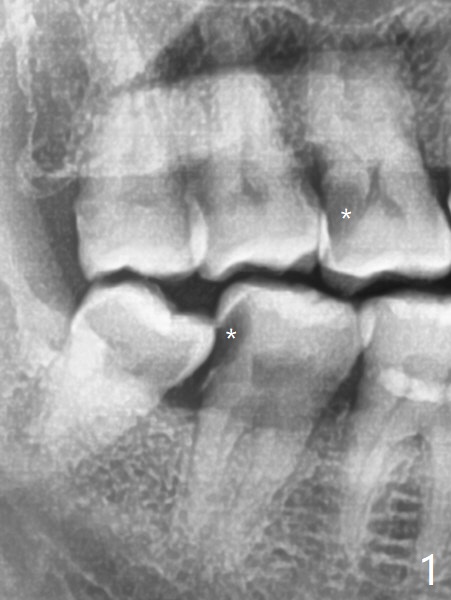

七天后缝线消失,伤口仿佛愈合,右下七没有症状。右上第一磨牙DO树脂修复,好像接近远中舌侧牙髓角,术后全景片(图三)似乎证实这一点。